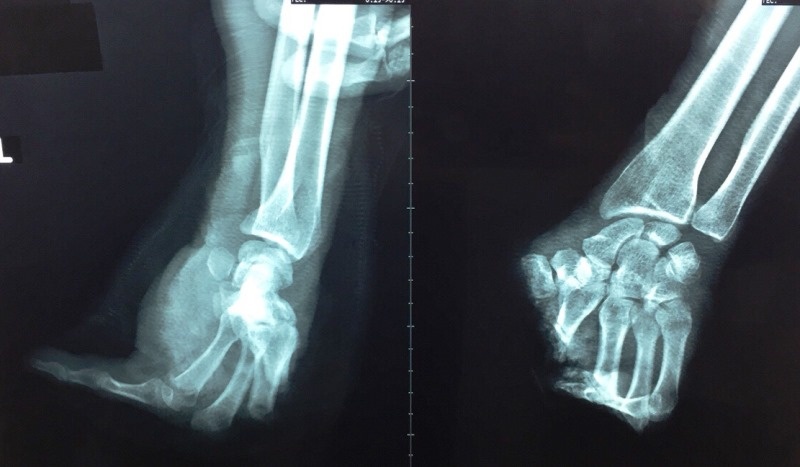

| Hình chụp X-quang bàn tay bị đứt lìa của nạn nhân. Ảnh: Hòa Khánh |